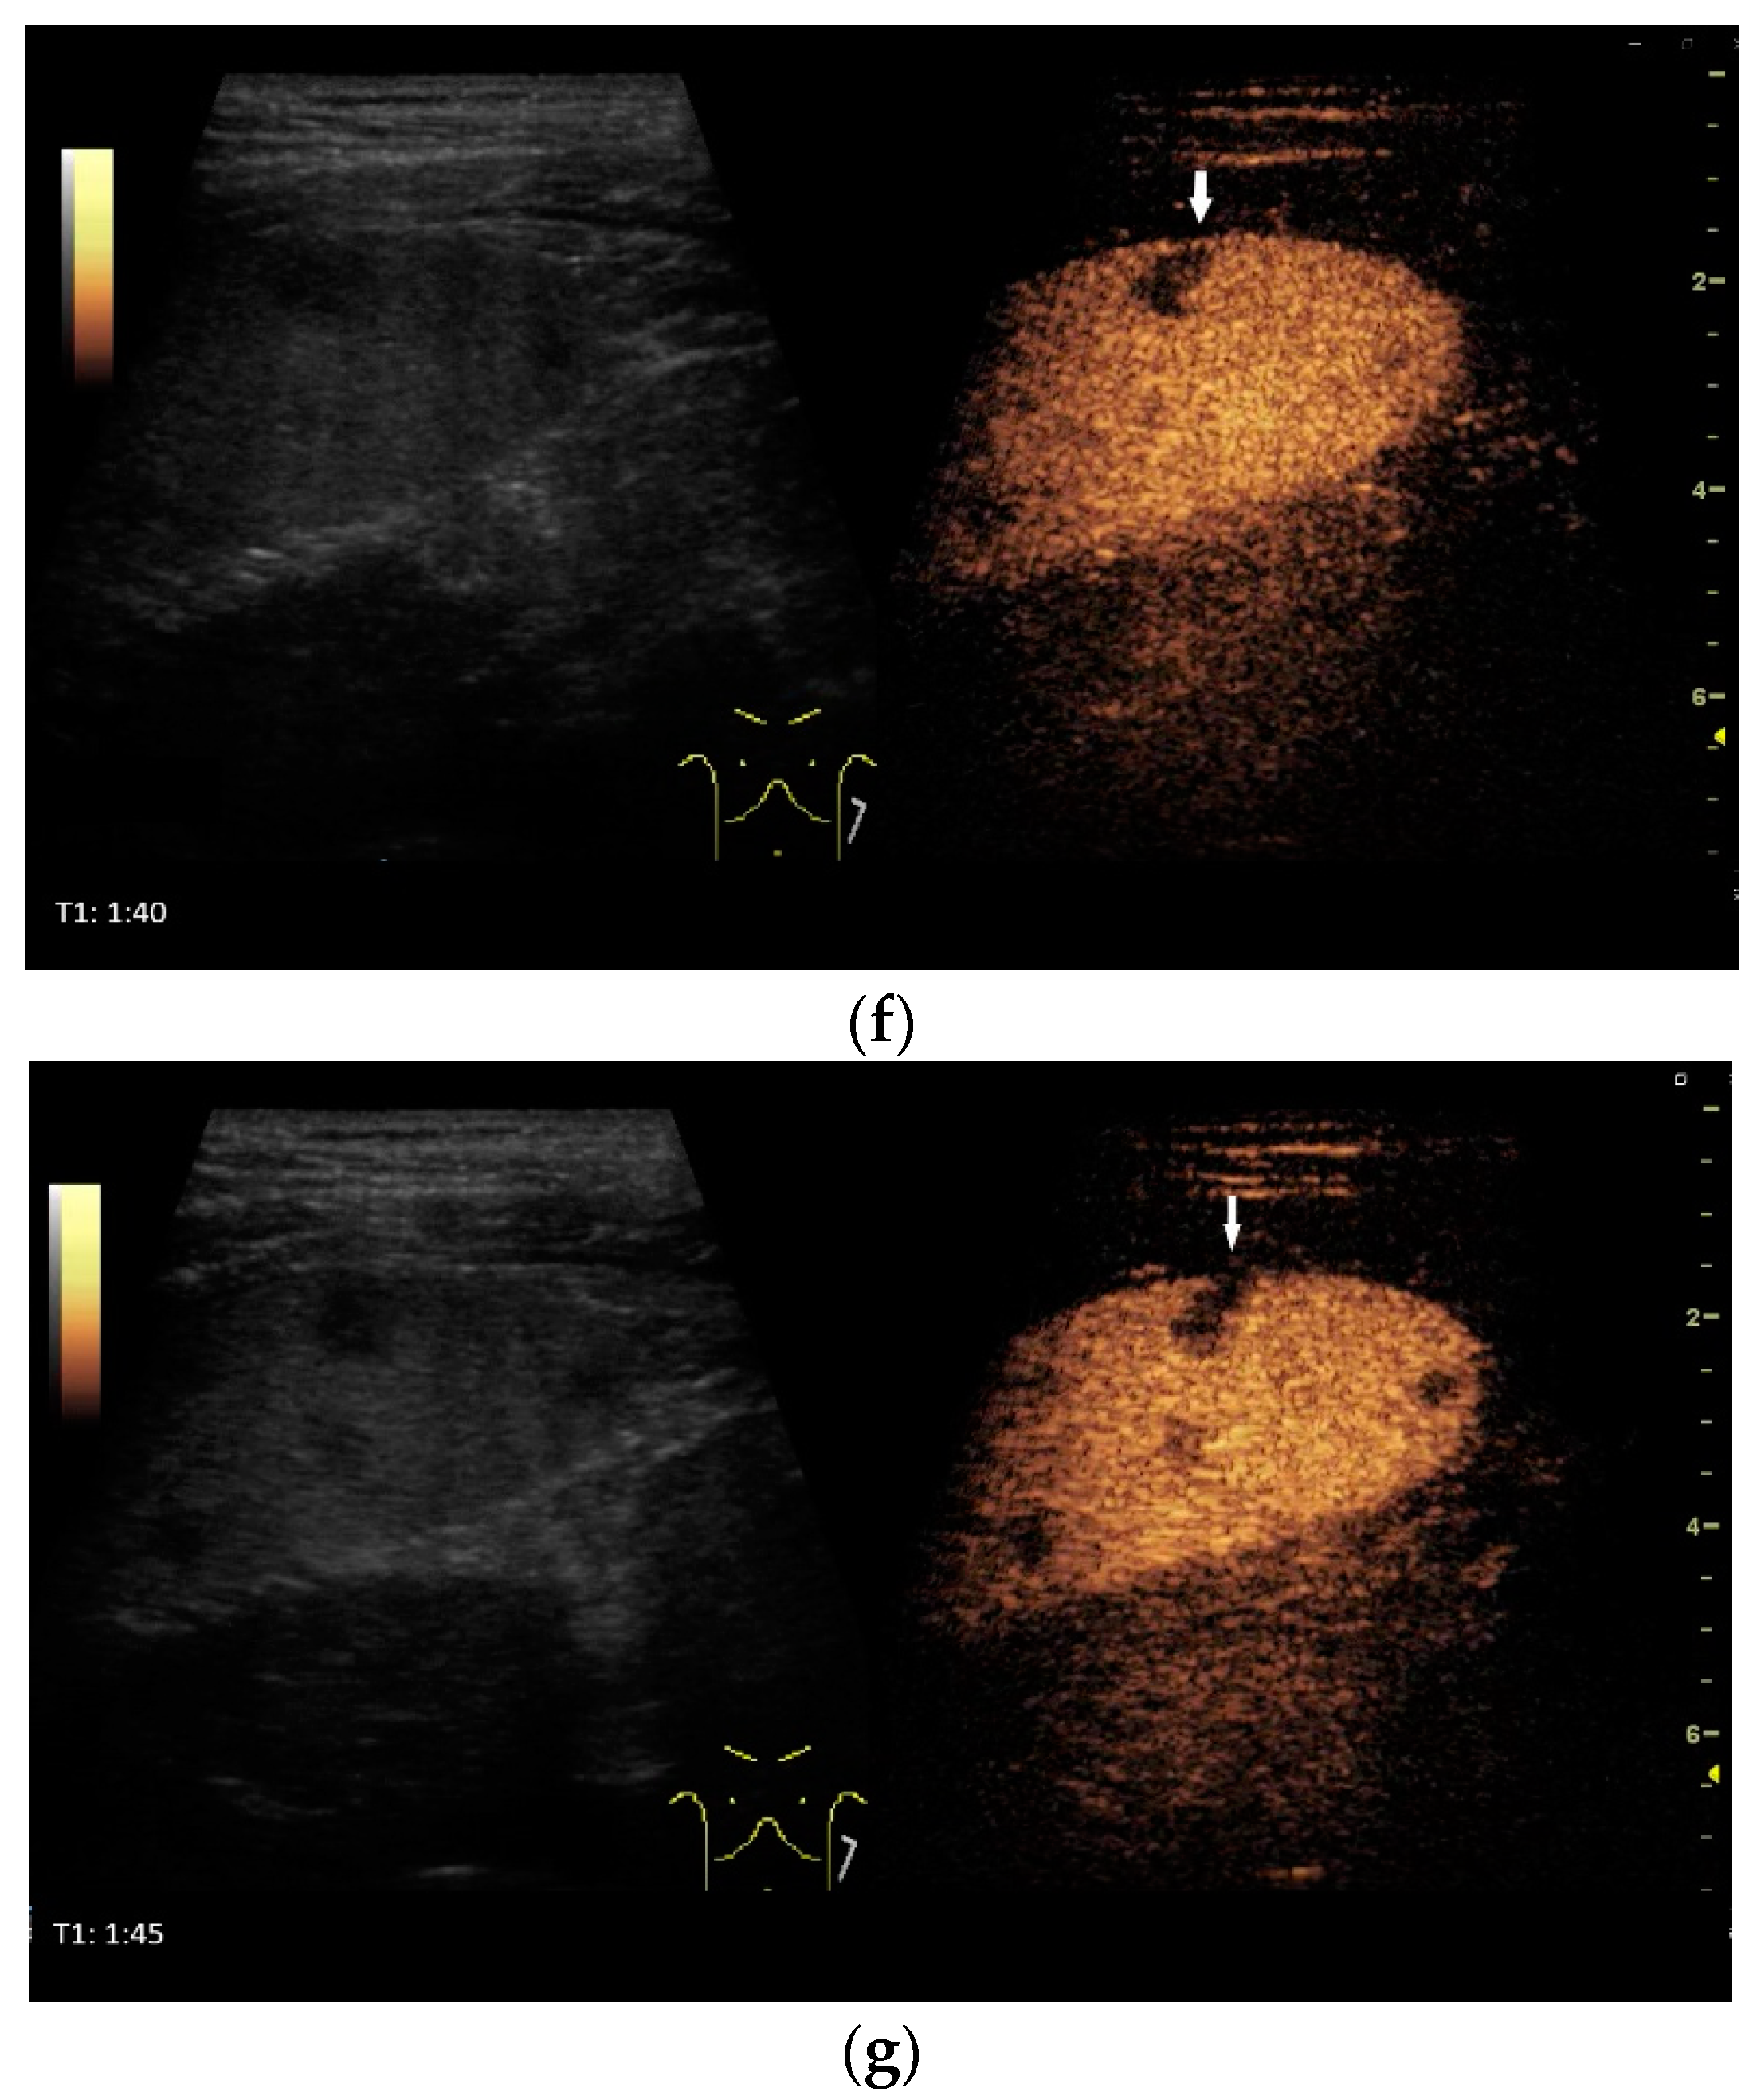

What can be seen sonographically? Ascites can be either diffuse or focal type [Figure 1a,b]. Due to the protein and cell content, these tend to be echogenic, rather than non-echoic. Attention must be paid to enlarged lymph nodes at the same time. Any thickening of the peritoneum and mesentery must be specifically searched for. This also applies to macronodular changes in the peritoneum and mesentery [Figure 1c–h]. The smallest speck-like deposits are usually not visible on ultrasound [36]. With ascites, it may be possible to observe the adhesions [31,37]. Kumar et al. were able to histologically detect granulomatous inflammation in 17/19 (89%) patients using ultrasound-guided needle biopsy of omental thickenings. In a country like India, the authors interpreted this as a manifestation of tuberculosis [32].

Figure 1.

Typical changes in the peritoneum, mesentery, and omentum in patients with tuberculosis. Ascites with pronounced septa (a). Ascites encapsulated between the abdominal wall and colon (b). Omental thickening with non-echoic caseous abscesses and few echogenic contents (c); hypoechoic nodules in hyperechoic thickened peritoneum (d). Significantly thickened hyperechoic peritoneum in B-mode US (right side of image) (marked with arrows). In CEUS, the thickened peritoneum is contrast enhanced in the arterial phase (e). In the parenchymal phase, it shows a decrease in enhancement (f). The thickened hyperechoic peritoneum shows a non-echoic lesion (arrow) (g). In the CEUS, this is not enhanced and instead shows a hyperenhanced rim. This corresponds to caseous necrosis (h).